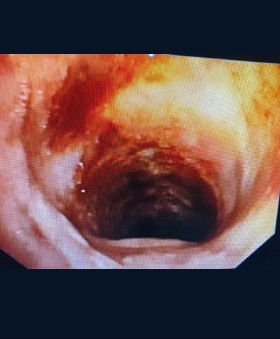

Patient was intubated using a rigid bronchoscope (EFER DUMON, 10.00/9.20 mm tracheal tube) after induction with fentanyl and propofol. The procedure was done under total intravenous anaesthesia. After successful intubation with the rigid bronchoscope, flexible bronchoscope was passed through the rigid scope. A 4mm MLS endotracheal tube with standard cuff was passed next to the rigid bronchoscope and was positioned beyond the tumour with cuff inflated at about 4 cm above the carina. This approach helps the endoscopist to have total control of the ventilation through out the procedure. Initial attempt was made to cut the stalk of the tumour using an electrosurgical snare, but was unsuccessful as the tumour was attached on to the trachea at multiple sites. Tumour destruction was performed using argon plasma coagulation probe. Non-contact APC was used initially to achieve deep coagulation and effective devitalization of the tumour. After effective coagulation, the cryoprobe was pressed in to the tumour and freezing was performed. The tumour was removed with cryo-extraction technique by repeatedly freezing the tumour and extracting it until the complete tumour is removed from the lumen of the trachea. The tumour base is coagulated using APC probe and contact tamponade with the rigid tracheoscope barrel. Patient is extubated immediately after the procedure.

There were no intra-operative and post-operative procedural complications. Histopathology of the tumour was reported as squamous cell carcinoma. Repeat CT post procedure revealed complete patency of the tracheal lumen with mild wall thickening and irregularity. The patient is being treated with External Beam radiation therapy by the oncology team.

Before

After